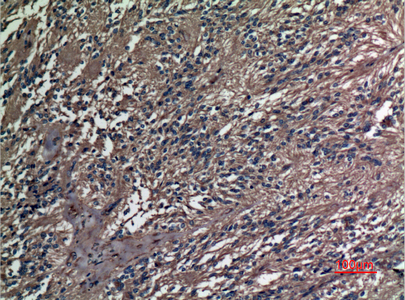

分类: 科研抗体货号: P23532别名: CD265; FEO; LOH18CR1; mRANK; ODFR; OFE; OPTB7; OSTS; PDB2; RANK; TNFRSF11A; TRANCER应用: WB,IHC反应种属: Human,Mouse,Rat